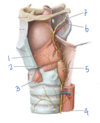

Which structure is labeled by #7?

Hypoglossal nerve (CN XII)

- Inferior to the lingual and glossopharyngeal nerves

- Lingual from CN V3, labeled #2 here

- Glossopharyngeal CN IX, labled #4 here

Which structure is labeled by #7?

Internal carotid artery

(Also #10)

Which structure is labeled by #6?

What is its action?

Recurrent laryngeal nerve

- Motor innervation to laryngeal muscles except cricothyroid muscle

- Visceral sensory below vocal cords

(Internal laryngeal nerve is visceral sensory above vocal cords, external laryngeal is motor to the cricothyroid muscle)